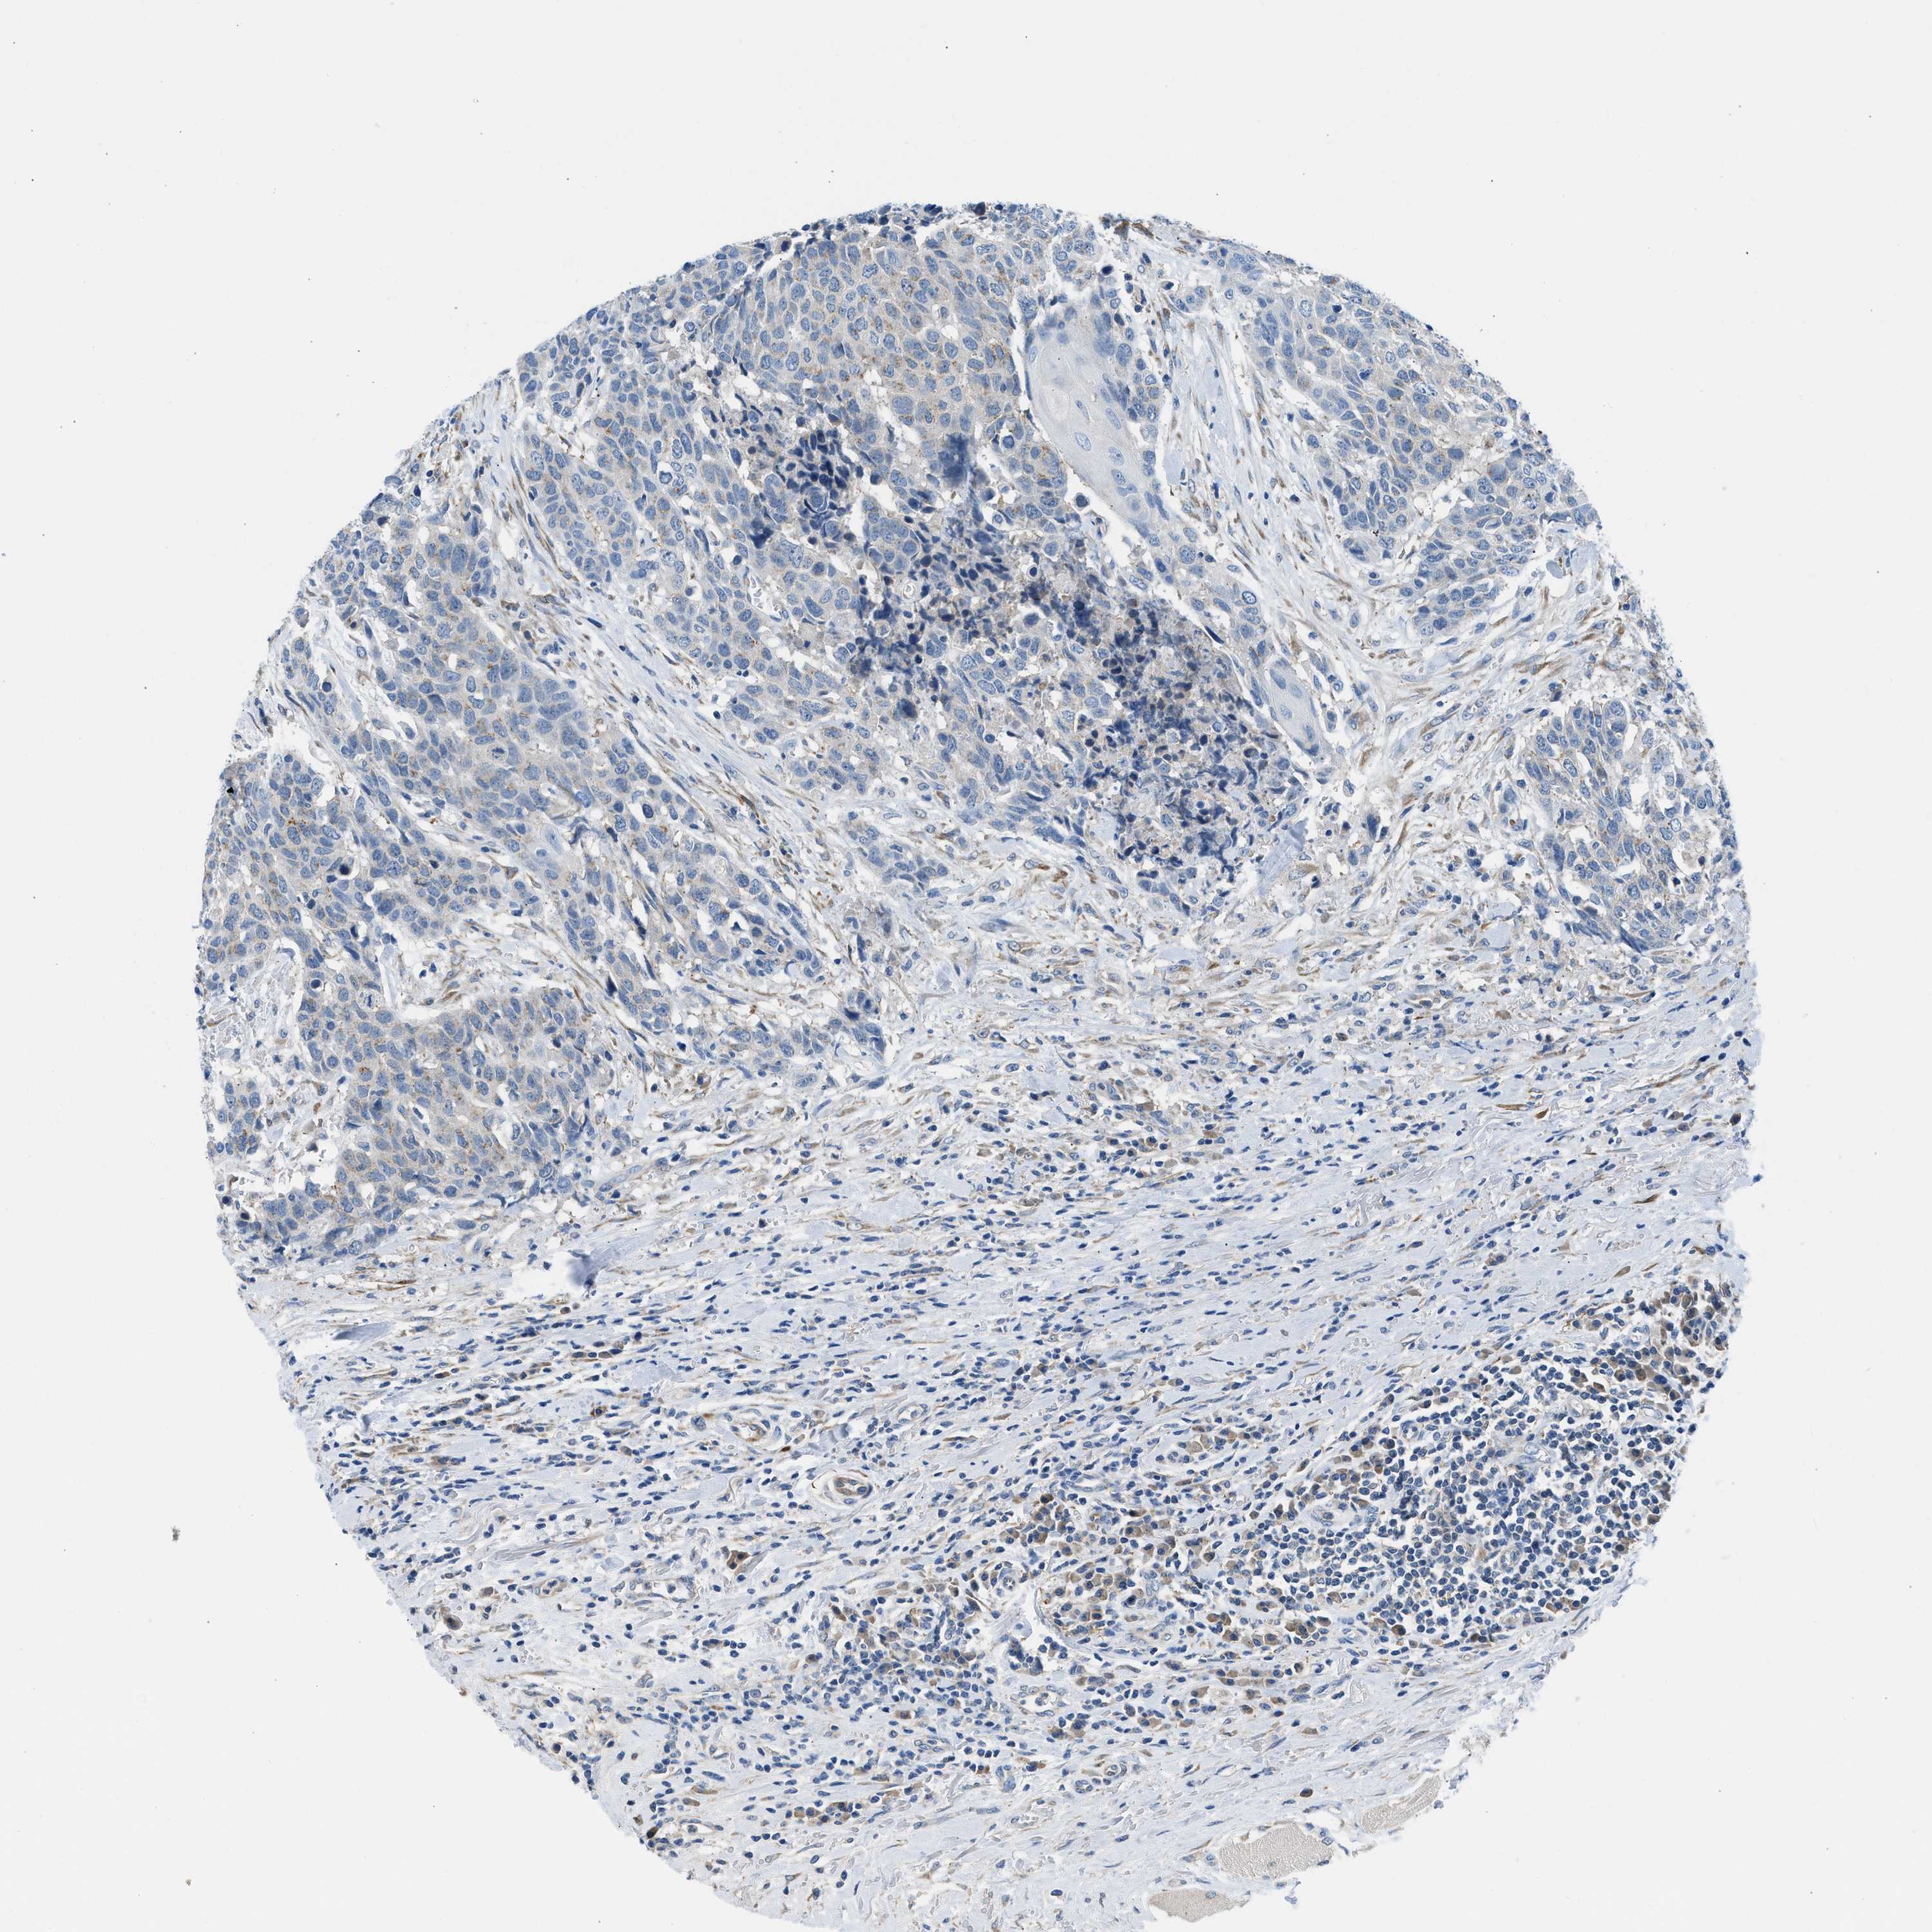

HEAD AND NECK CANCER - Protein expressioni

A mouse-over function shows sample information and annotation data. Click on an image to view it in a full screen mode. Samples can be filtered based on level of antibody staining by selecting one or several of the following categories: high, medium, low and not detected. The assay and annotation is described here.

Antibody stainingi

Antibody staining in the annotated cell types in the current human tissue is reported as not detected, low, medium, or high, based on conventional immunohistochemistry profiling in selected tissues. This score is based on the combination of the staining intensity and fraction of stained cells.

Each image is clickable and will lead to virtual microscopy that enables deeper exploration of all samples and also displays staining intensity scores, fraction scores and subcellular localization as well as patient and tissue information for each sample.

Antibody HPA018525

Staining

High

Medium

Low

Not detected

Intensity

Strong

Moderate

Weak

Negative

Quantity

>75%

75%-25%

<25%

None

Location

Nuclear

Cytoplasmic/membranous

Cytoplasmic/membranous,nuclear

Squamous cell carcinoma, NOS